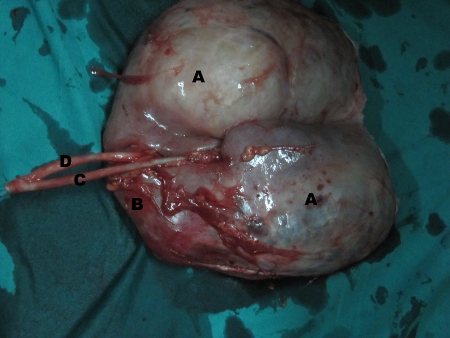

On exploration, there was a large hydatid cyst in the upper moiety of right incomplete duplex kidney, compressing the lower moiety into thin rim of parenchyma with two separate ureters that were united caudally. Heminephrectomy was not feasible, so a simple nephrectomy was done. Cut specimen of the right kidney had two moieties with two ureters. The upper moiety was turned into a bag of cysts while lower moiety had compressed thinned out renal parenchyma with no evidence of any cystic disease (Fig. 2,3). The histopathological examination of the cyst was consistent with the diagnosis of hydatid disease of kidney. Albendazole was continued for eight weeks after surgery. USG abdomen after 6 months suggested no recurrence.

[Figure ID: F2]

[Figure ID: F3]